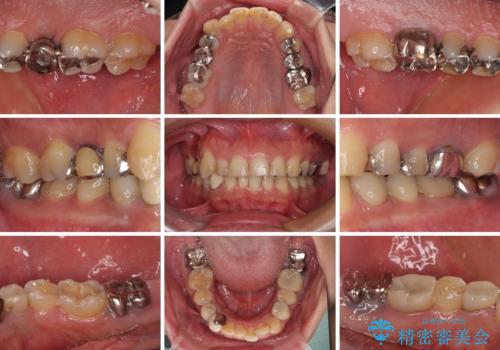

- 近医にて下顎奥歯の抜歯が必要と言われたとのことで来院された患者様です。

診察の結果、奥歯は左右ともに抜歯が必要な状態でした。

他の銀歯も気になっており、セラミックにしたいとの要望があり、詳しくお話をすると、デコボコの歯ならびも整えたいとのことでした。

抜歯が必要な歯は事前に抜歯をし、その後ワイヤー装置にて歯列矯正を行い、途中でインプラントを埋入し、オールセラミッククラウンにて補綴治療を行うこととしました。